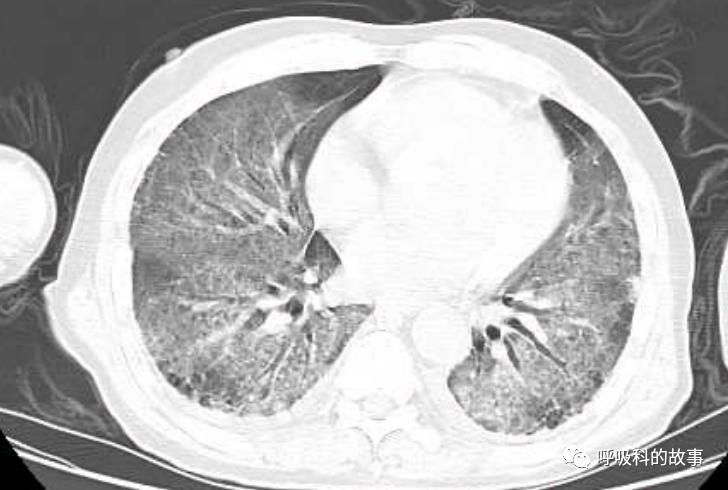

上周,我去会诊一个病人又出现了类似的情况,一个72岁的男性病人因为发生十二指肠球部溃疡穿孔入住我院胃肠外科,给予腹腔镜下十二指肠球部溃疡穿孔修补术。术后由于患者禁食就给予了大量的补液,大约有3000多毫升,其中0.9%氯化钠盐水(也就是我们通常所说的生理盐水)一共是补了接近2000ml,同时还补了1500ml的营养液呢。患者术后第二天晚上开始出现呼吸困难,程度进行性加重,到了术后的第五天,呼吸困难非常明显了,病人也出现端坐位呼吸,两肺出现严重的肺水肿转入ICU治疗。